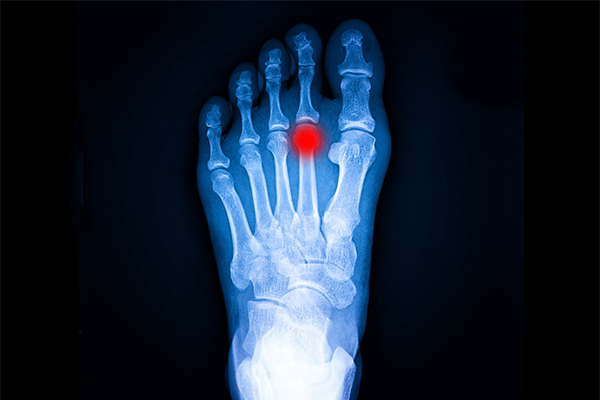

Enfermedad de Freiberg: Causas, síntomas y tratamiento

La enfermedad de Freiberg es una patología ósea poco frecuente que afecta a la cabeza del segundo metatarsiano, provocando dolor en el antepié y limitación